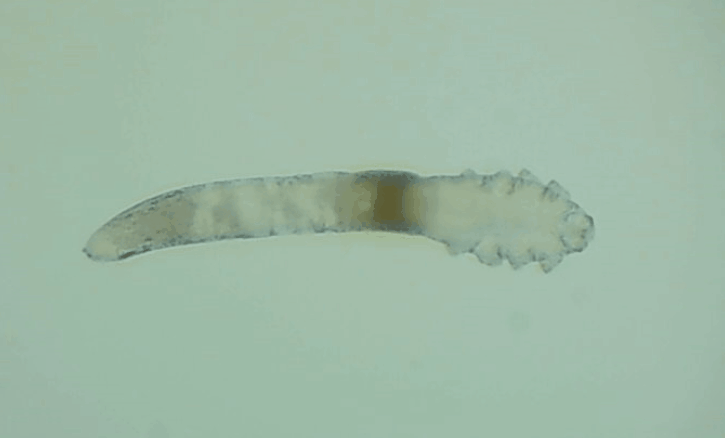

是的, 眼睛也會(huì)有蟲子,那就是蠕形螨。眼睛發(fā)紅、干癢、疲勞、睫毛脫落,這些都是因?yàn)樗?/div>

其實(shí)蠕形螨主要活動(dòng)在毛囊和皮脂腺中,以皮膚碎屑和腺體分泌物作為食物來源,而睫毛根部的瞼板腺是排泄油脂的重要部位,因此眼睫毛和瞼板腺也是螨蟲的主要活動(dòng)場所。

一般來說,15天內(nèi),一只蠕形螨會(huì)在你眼睛里產(chǎn)下50只蟲卵。如果不及時(shí)除螨,它們會(huì)迅速繁殖,從而導(dǎo)致睫毛脫落、亂生、眼睛紅癢,甚至引發(fā)眼部炎癥。如果影響到角膜,就會(huì)造成視力下降甚至失明。

在廈門眼科中心檢查后發(fā)現(xiàn),在她的眼睛上竟然有大量的螨蟲,僅是檢查用的2、3根睫毛上就有8只,除螨蟲外,她的眼睛還出現(xiàn)了瞼緣炎以及干眼癥。